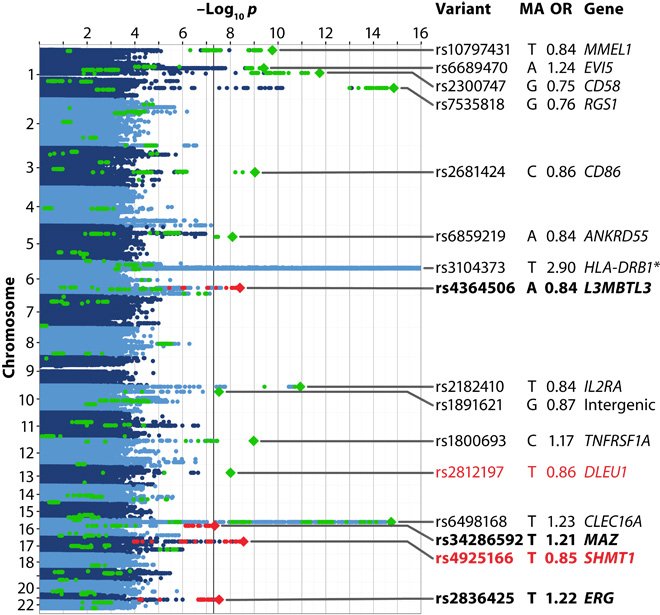

A study of 4,000 German patients explores risk factors for MS: http://scim.ag/1ZUoKXI

#ScienceAdvancespic.twitter.com/kZ281ae5Wg